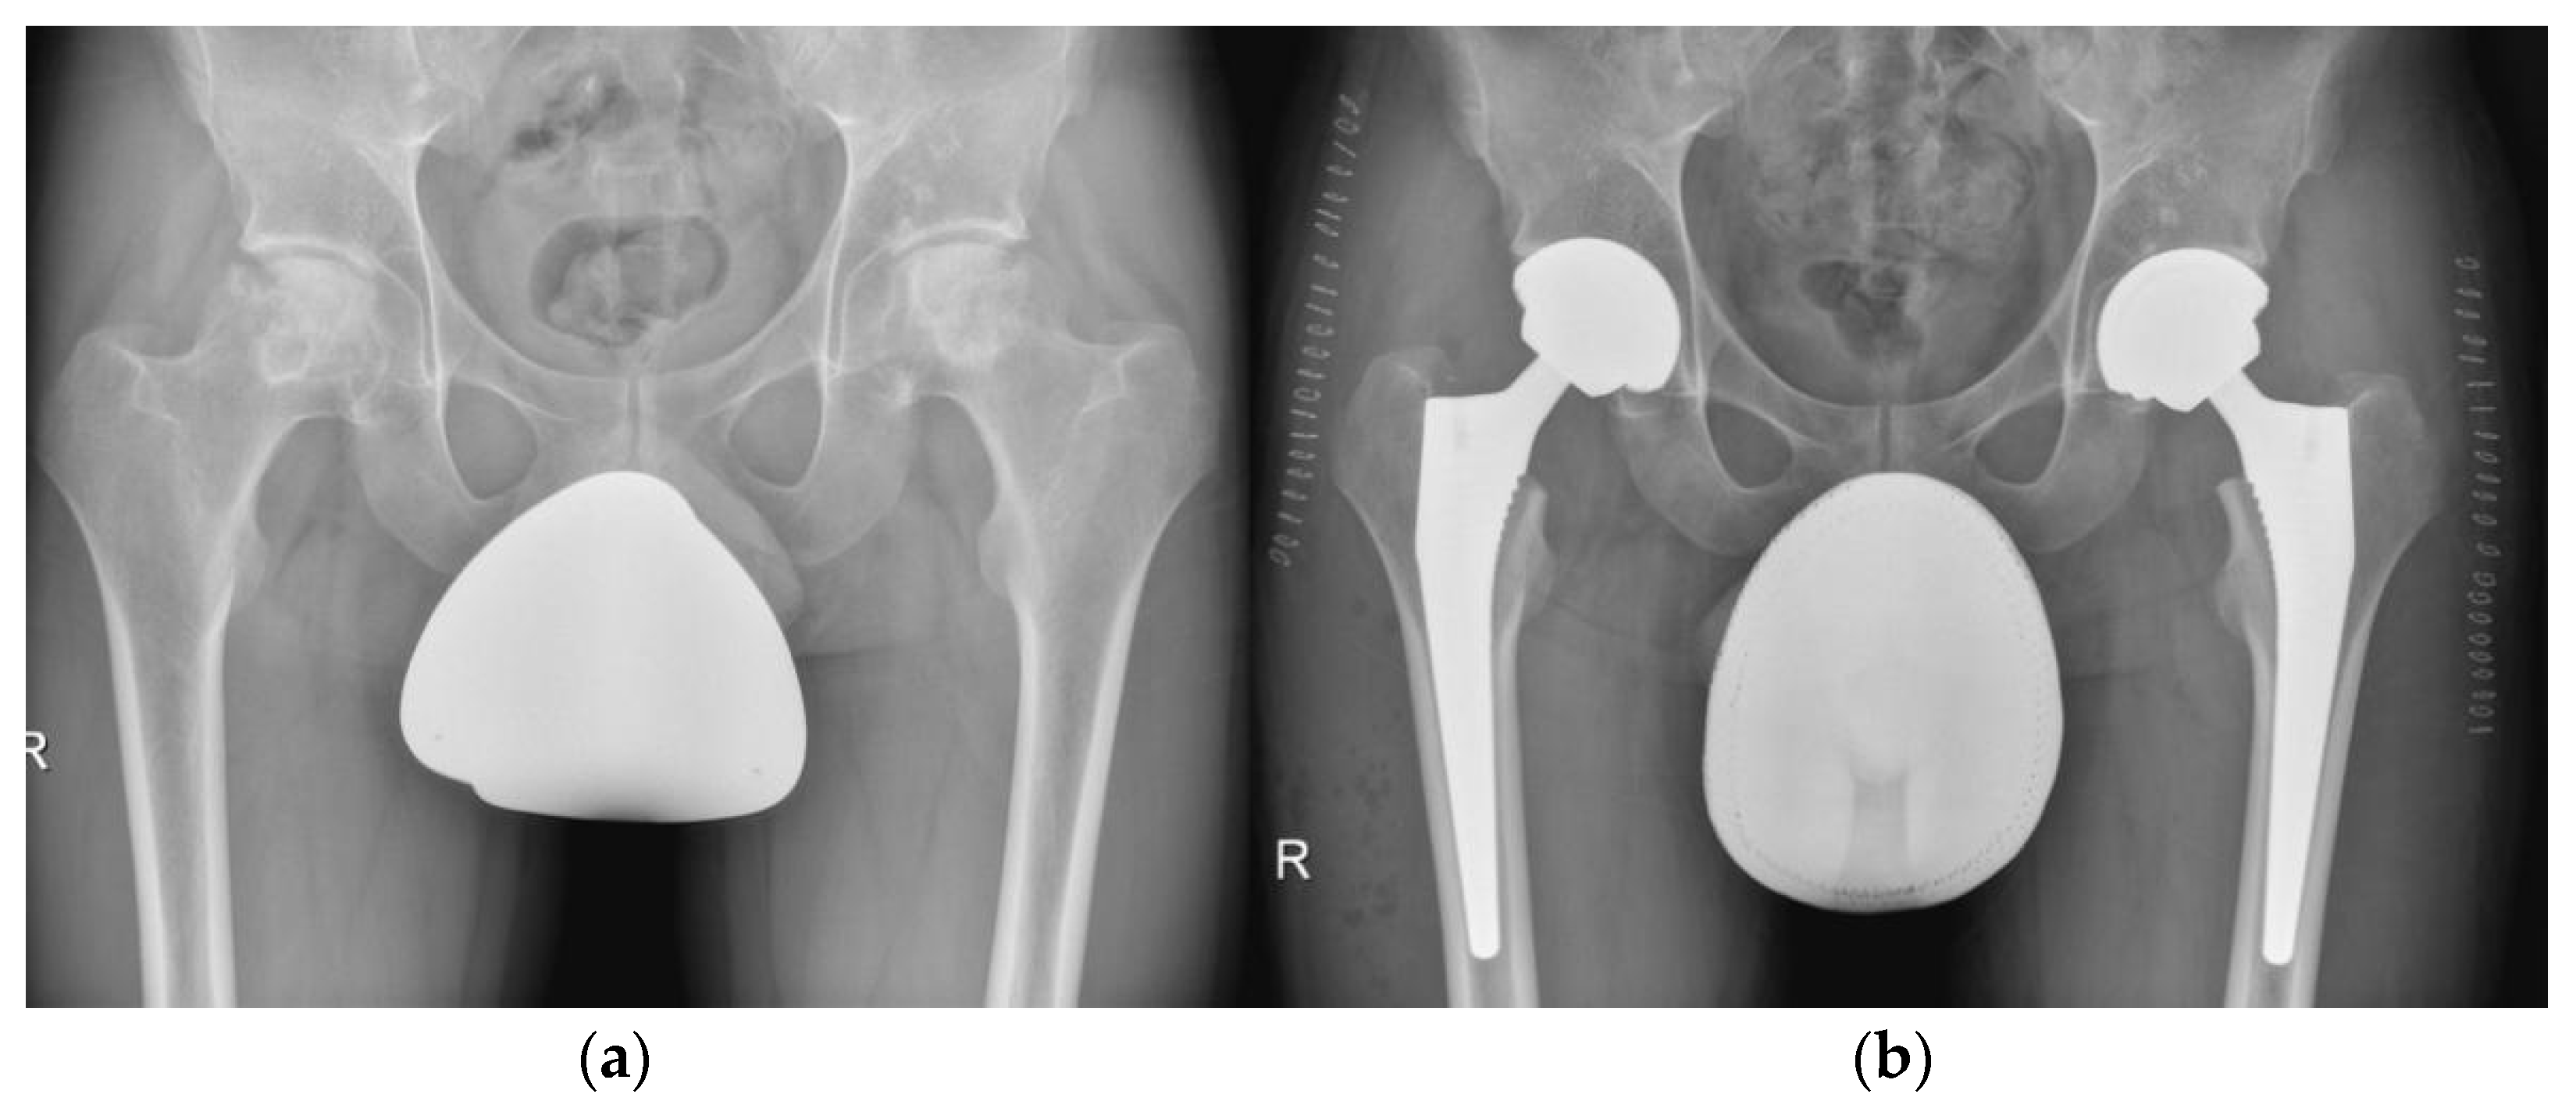

5.5. Hip

- Mellon, S.J.; Liddle, A.D.; Pandit, H. Hip Replacement: Landmark Surgery in Modern Medical History. Maturitas 2013, 75, 221–226. [Google Scholar] [CrossRef]

- Zagra, L. Advances in Hip Arthroplasty Surgery: What Is Justified? EFORT Open Rev. 2017, 2, 171–178. [Google Scholar] [CrossRef]

- Learmonth, I.D.; Young, C.; Rorabeck, C. The Operation of the Century: Total Hip Replacement. Lancet 2007, 370, 1508–1519. [Google Scholar] [CrossRef]

- Kovac, S.; Pisot, V.; Trebse, R.; Rotter, A. Fifty-One-Year Survival of a Judet Polymethylmethacrylate Hip Prosthesis. J. Arthroplast. 2004, 19, 664–667. [Google Scholar] [CrossRef]

- Salih, S.; Hamer, A. Hip and Knee Replacement. Surg. Oxf. 2013, 31, 482–487. [Google Scholar] [CrossRef]

- Trebše, R.; Valič, M.; Savarin, D.; Milošev, I.; Levašič, V. Survival Rate of Total Hip Replacements with Matched and with Mixed Components with 10.7 Years Mean Follow-Up. Hip Int. J. Clin. Exp. Res. Hip Pathol. Ther. 2022, 32, 32–38. [Google Scholar] [CrossRef] [PubMed]

- Girard, J. Hip Resurfacing: International Perspectives: Review Article. HSS J. 2017, 13, 7–11. [Google Scholar] [CrossRef]

- Kaiser, D.; Kamath, A.F.; Zingg, P.; Dora, C. Double Mobility Cup Total Hip Arthroplasty in Patients at High Risk for Dislocation: A Single-Center Analysis. Arch. Orthop. Trauma Surg. 2015, 135, 1755–1762. [Google Scholar] [CrossRef]